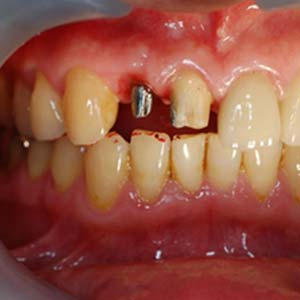

王先生十幾年前的假牙脫落了,一經檢查後右上側門牙蛀掉了, 由於牙齒結構剩下過少無法再製作假牙

即拔即種

經過講解溝通後,選擇使用"即拔即種"微創植牙的處理方式

拔除殘留牙根

當日在拔除牙齒後,立即在拔牙窩洞裡,置入適當尺寸的植體,並在使用人工骨粉填塞縫隙。